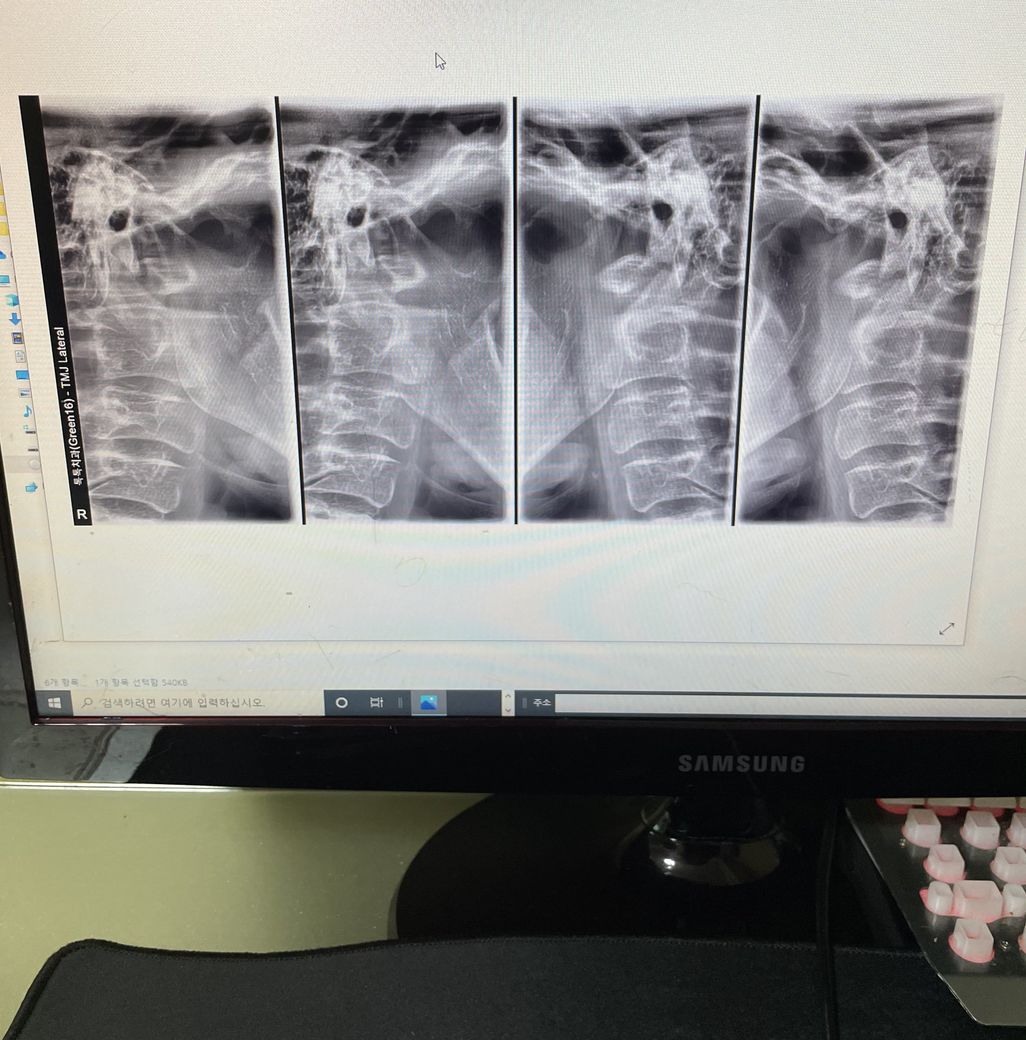

턱관절염 4기 퇴행성 턱관절염

구강내과를 가보니 턱관절염 4기고 가망이 없는 상태라네요 턱관절염 4기 인가요?? 의사선생님이 가망이 없다고ㅠㅠ 많이 심각한가요?? 밥먹고 양치하고는 가능한데

해당 사진만으로는 골관절염을 정확히 판단하기에는 무리가 있습니다. 보통 ct까지 같이 보게 되며 골관절염이라는 것은 해당 부위에 염증이 심하고 그에 따라 턱도 비대칭이 있을 것으로 보입니다. 보통 이때는 가망이 없다라기보다는 더 이상 진행되지 않기 위해 약을 쓰거나 통증 및 불편감을 조절하는데 앞으로 힘쓰는 것이 맞습니다.